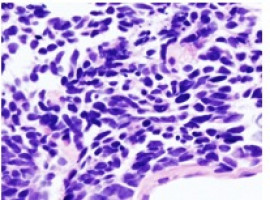

Gastrointestinal stromal tumours (GISTs) arise most frequently in the stomach and small intestine, but can be found anywhere in or near the gastrointestinal tract.